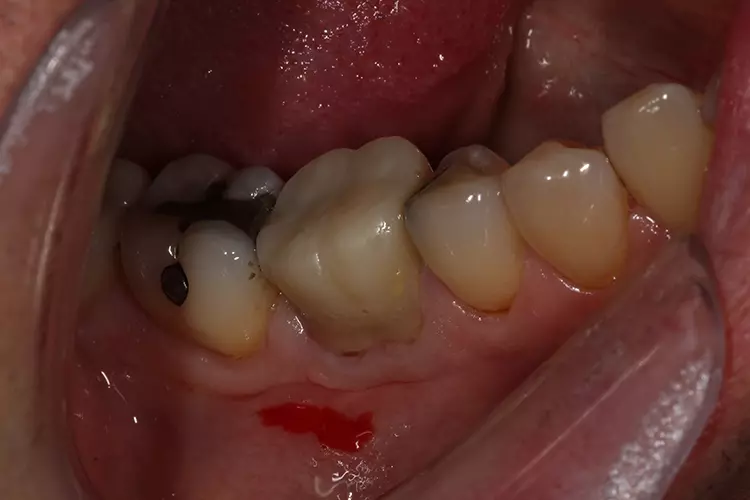

Die Präparation für die neue Krone erfolgte mit konischen Fräsern grober und mittlerer Körnung (850.014C/M, Solo Diamond). Nach der Kariesentfernung war eine Anhebung der tief liegenden Kavitätenränder erforderlich, die ebenso wie auch der Aufbau des restlichen Stumpfes mit VisCalor bulk (VOCO) erfolgte. Um eine Weichgewebskonditionierung zu ermöglichen, wurde eine provisorische Krone hergestellt, die der Patient vor der digitalen Abformung einige Wochen getragen hat (Abb. 2a und 2b).

Die provisorische Krone wurde mit Komposit auf der distalen Seite verstärkt. Zur morphologischen Adaptation des Weichgewebes trug der Patient die provisorische Krone für einige Wochen. So konnten gleichzeitig die Bedingungen für eine präzise Abformung geschaffen werden.

Die provisorische Krone wirkt etwas unförmig (Abb. 2), was auf die mangelnde Ästhetik der ursprünglichen Krone zurückzuführen ist. VOCO Retraction Paste ist ein pastöses Produkt, das in einem Cap zur direkten Anwendung erhältlich ist. Es hat ausgezeichnete adstringierende Eigenschaften und hinterlässt, wie in diesem Fall zu sehen ist, einen trockenen und gut geweiteten trockenen Sulkus – ideale Voraussetzungen für eine hochpräzise Abformung.